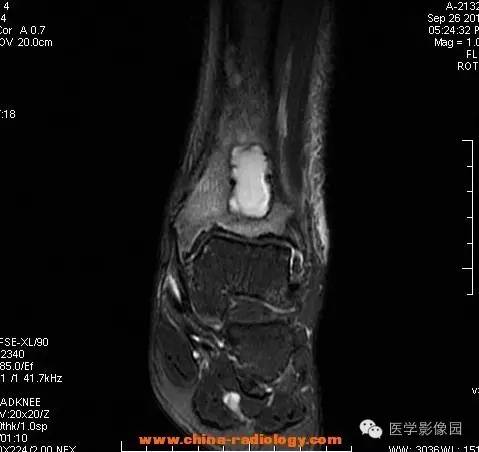

影像学表现:胫骨中下段干骺端不未规则形长T1长T2信号,T2WI见不完整环形稍低信号影,T2脂肪抑制低信号更明显,并见胫骨下段及踝关节后外侧软组织呈弥漫稍高信号,增强明显不均匀强化,增强见低信号环内有环形强化影。

影像学表现:表现为长骨干骺端有椭圆形密度减低区,边缘有清晰的骨质硬化,病变与邻近正常骨髓腔境界清楚。MRI上T1WI呈低信号,少数呈等信号,T2WI多为混杂高信号,增强扫描可见环状强化,强化的脓肿壁薄而均匀。